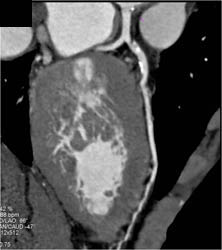

Plaque in LAD